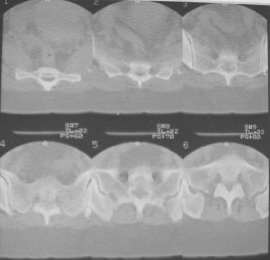

Из анамнеза: в ноябре 2002г. оступилась,упалана трап самолета (на верхней площадке, сразу при выходе из салона) на правый тазобедренный сустав, а затем - вниз на землю на ноги и ягодицы. Потеряла сознание от боли. Доставлена в больницу по месту жительства, лечилась консервативно с диагнозом кокцигодиния.На рентгенограмме от 27.11.02г. вывиха копчика не определяется (снимок идентичен представленной R-грамме от28.11.03г., кроме этого есть нормальная R-грамма копчика в боковой проекции).Через три недели стала ходить, но привести правую ногу в тазобедренном суставе не могла. Сейчас ходит отведя кнаружи правое бедро и голень, как ножку циркуля (фото 1). Неврологических нарушений нет. По просьбе врачаможет на 30-40 секунд поставить ноги вместе (фото 2). При этом испытывает сильную тянущую боль и ощущение "вывернутости" в правом тазобедренном суставе. Эти ощущения заставляют вновь отвести бедро. В положении лежа разогнуть бедро полностью не может из-за болей в ягодичной мышце (фото 3). Сгибание также ограничено из-за болей (фото 4). Отведение в положении лежа возможно в том же объеме, что и стоя (фото 5). Заподозрен старый разрыв правого крестцово-подвздошного сочленения.Выполнено R-исследование и КТ(в приложении). По-поводу деформации лонного сочленения выяснен гинекологический анамнез. Роды одни, нормальные в 22 года. Из роддома выписана на 8 сутки, нарушения походки не было, R-графия таза не проводилась. Вопросы на обсуждение: 1. Диагноз либо алгоритм дальнейшего обследования. 2. Лечебная тактика (в первую очередь возможность и целесообразность оперативного лечения).

Присоединияюсь к мнению д-ра Джолдаса Кульджанова - наиболее вероятно повреждение ацетабулярной губы - acetabular rim syndrome (ARS).

Отсутствие изменений сустава на КТ и обычных рентгенограммах, стойкие боли и ограничение подвижности в суставе - симптомы, характерные для повреждения ацетабулярной губы. ЯМР с контрастом или без должны прояснить картину.

Уважаемый Юрий Алексеевич, сделаны ли пациентке более дистальные срезы КТ с захватом области тазобедренного сустава? Учитывая давность травмы, могли присоединиться и дистрофические процессы в субхондральной кости головки и впадины. Изменения в капсуле будут хорошо видны на УЗИ, особенно в сравнении со здоровой стороной. Эффективность лечебно-диагностического введения гормональных препаратов, на мой взгляд, сомнительна ввиду давности патологического состояния. При такой стойкой и давней контрактуре без операции вряд ли можно обойтись. Под наркозом амплитуда на разгибание должна увеличиться, усилить эффект можно тено-миотомиями заинтересованных групп мышц, капсулотомией + в послеоперационном периоде хорошее консервативное противовоспатлительное лечение с укладками на разгибание.Что мешает приведению пока не ясно, во встретившихся в нашей работе аналогичных ситуациях причиной был формирующийся медиальный остеофит головки, выталкивающий её из впадины.